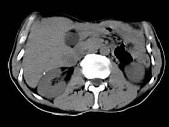

- 单项选择题根据所提供的图像,最可能的诊断是 ( )

A、转移癌

B、肝细胞癌

C、肝脓肿

D、肝血管瘤

E、以上都不是